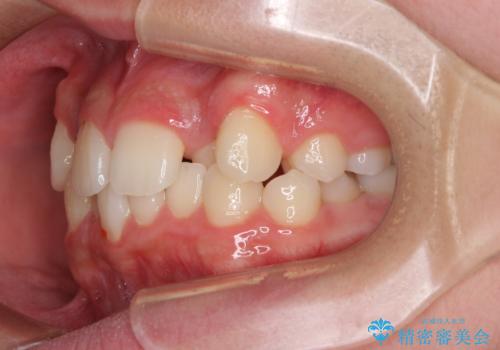

中学生のワイヤー矯正 クロスバイトを短期間で改善

- 前歯のクロスバイトを気にして来院された患者様です。

叢生のため磨き残しの多い歯列でしたが、1年弱で治療を終了でき、磨き残しや歯肉の腫れが著しく改善されました。